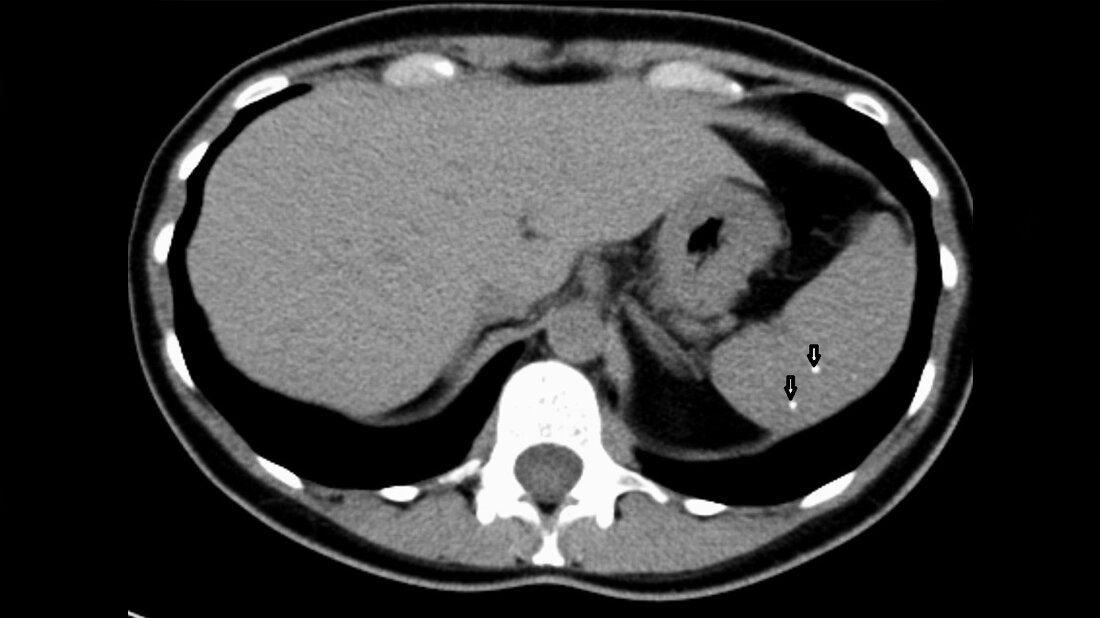

Phlebolithen sind „Venenkonkremente“ und stellen kleine Verkalkungen in venösen Gefäßen dar. Sie kommen häufig im Becken, können dort Harnleiterkonkremente vortäuschen, und in venösen Malformationen vor.

Phleboliths are “vein stones” and represent calcifications within venous structures. They are particularly common in the pelvis, where they may mimic ureteric calculi, and in venous malformations.